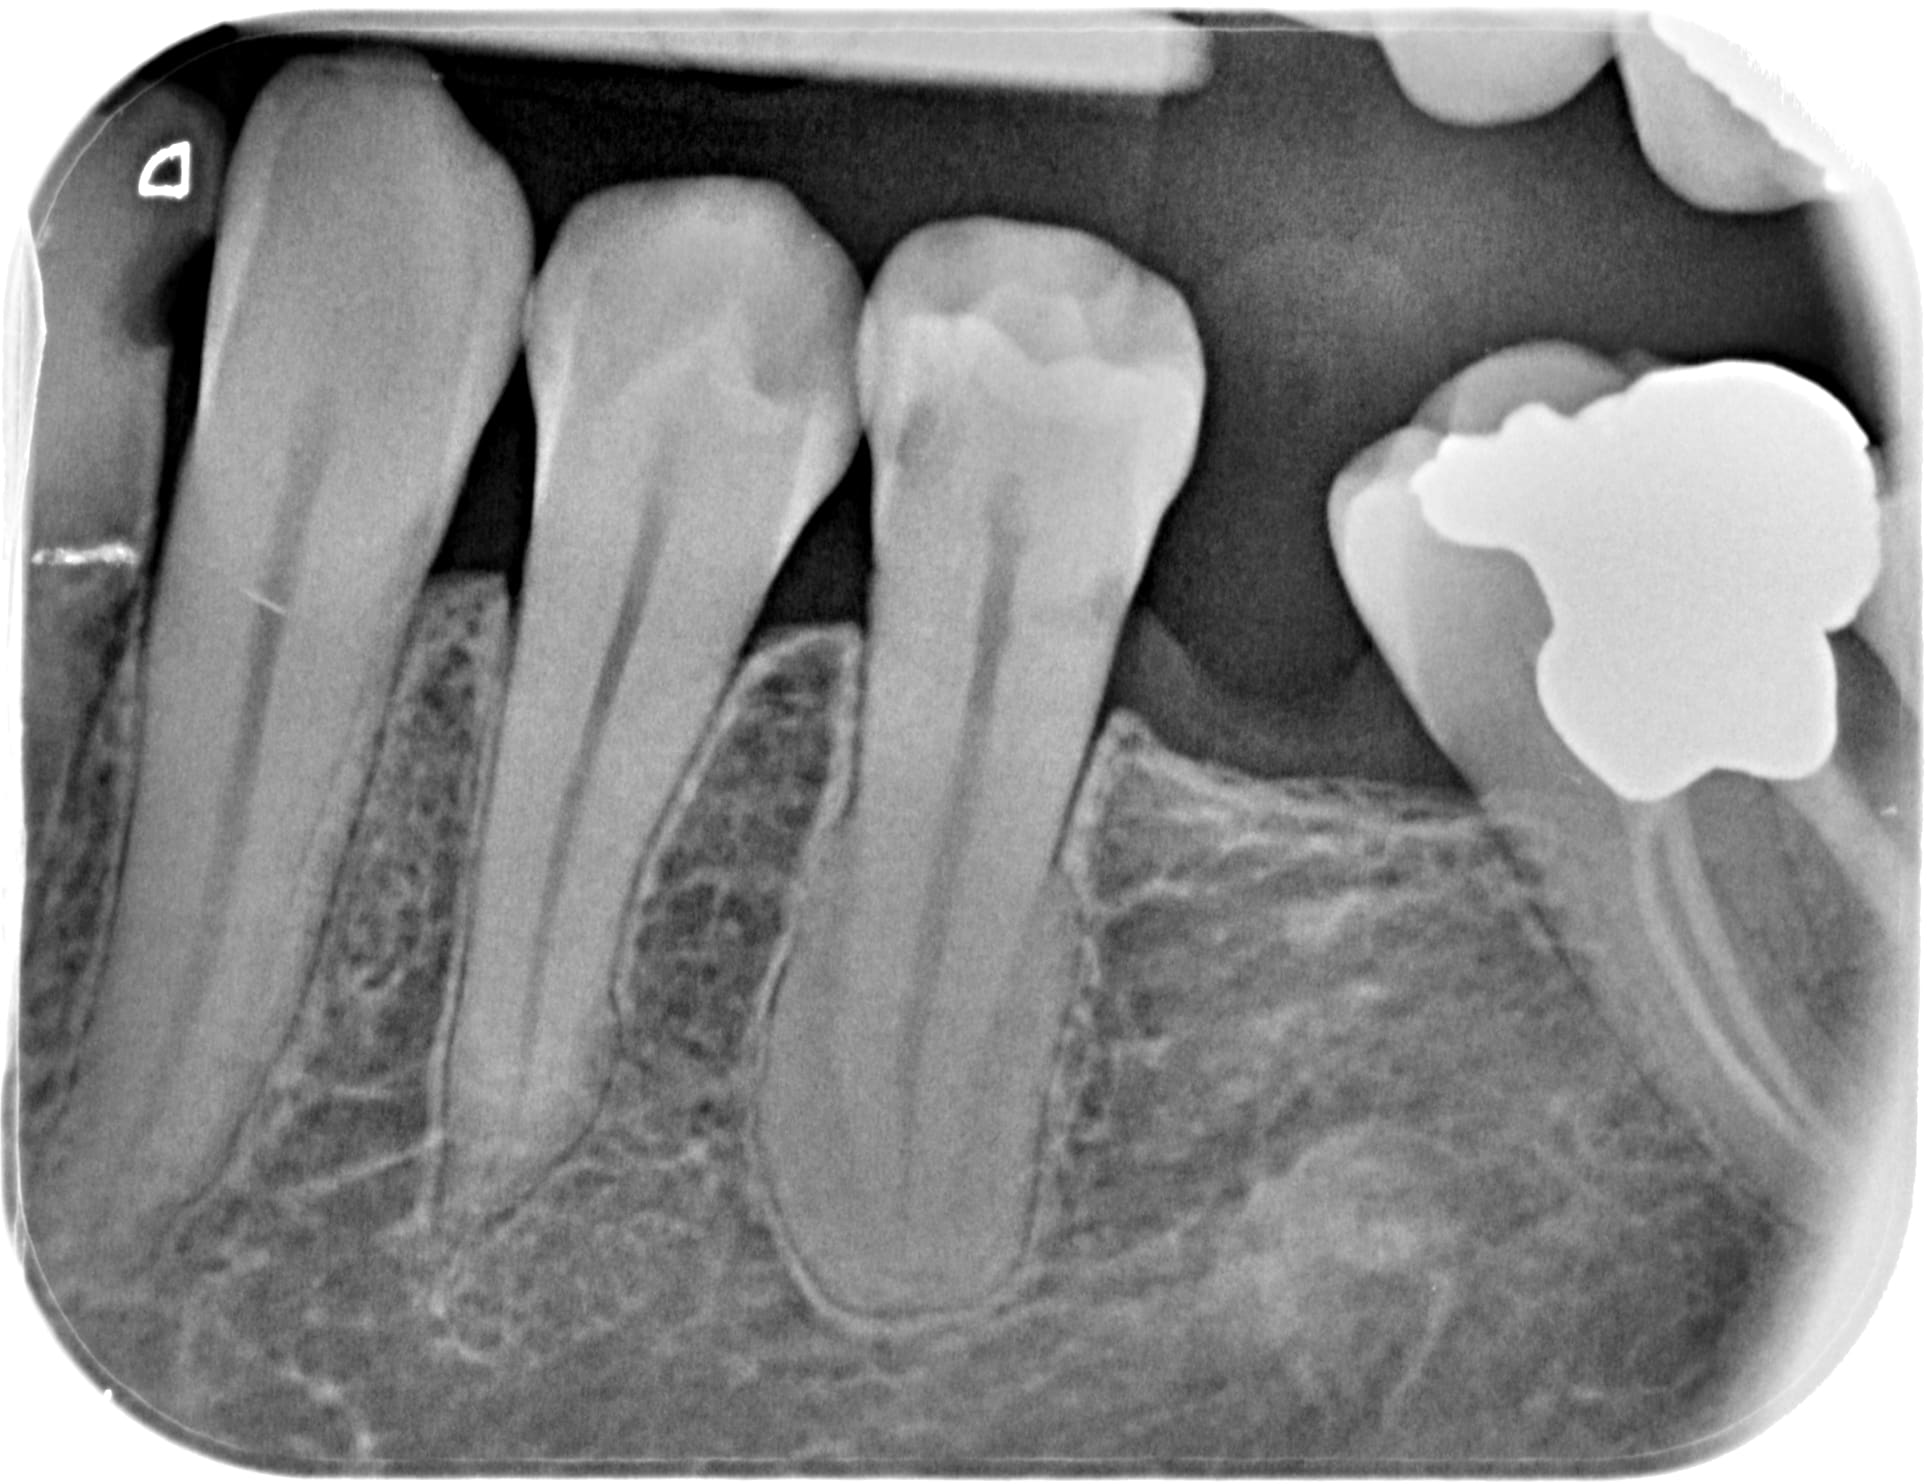

Je crois que j ai la meme chose que toi.

Mi mai j'en ai découvert un sur une 5 du bas chez une nouvelle patiente, totalement asymptomatique... je ne connais pas la conduite a tenir, si une âme charitable peut m'éclairer ce serait sympa.

Il lui manque déjà la 6 et la 7 a un pied dans la tombe...

Cementoblastome eelsrf - Eugenol